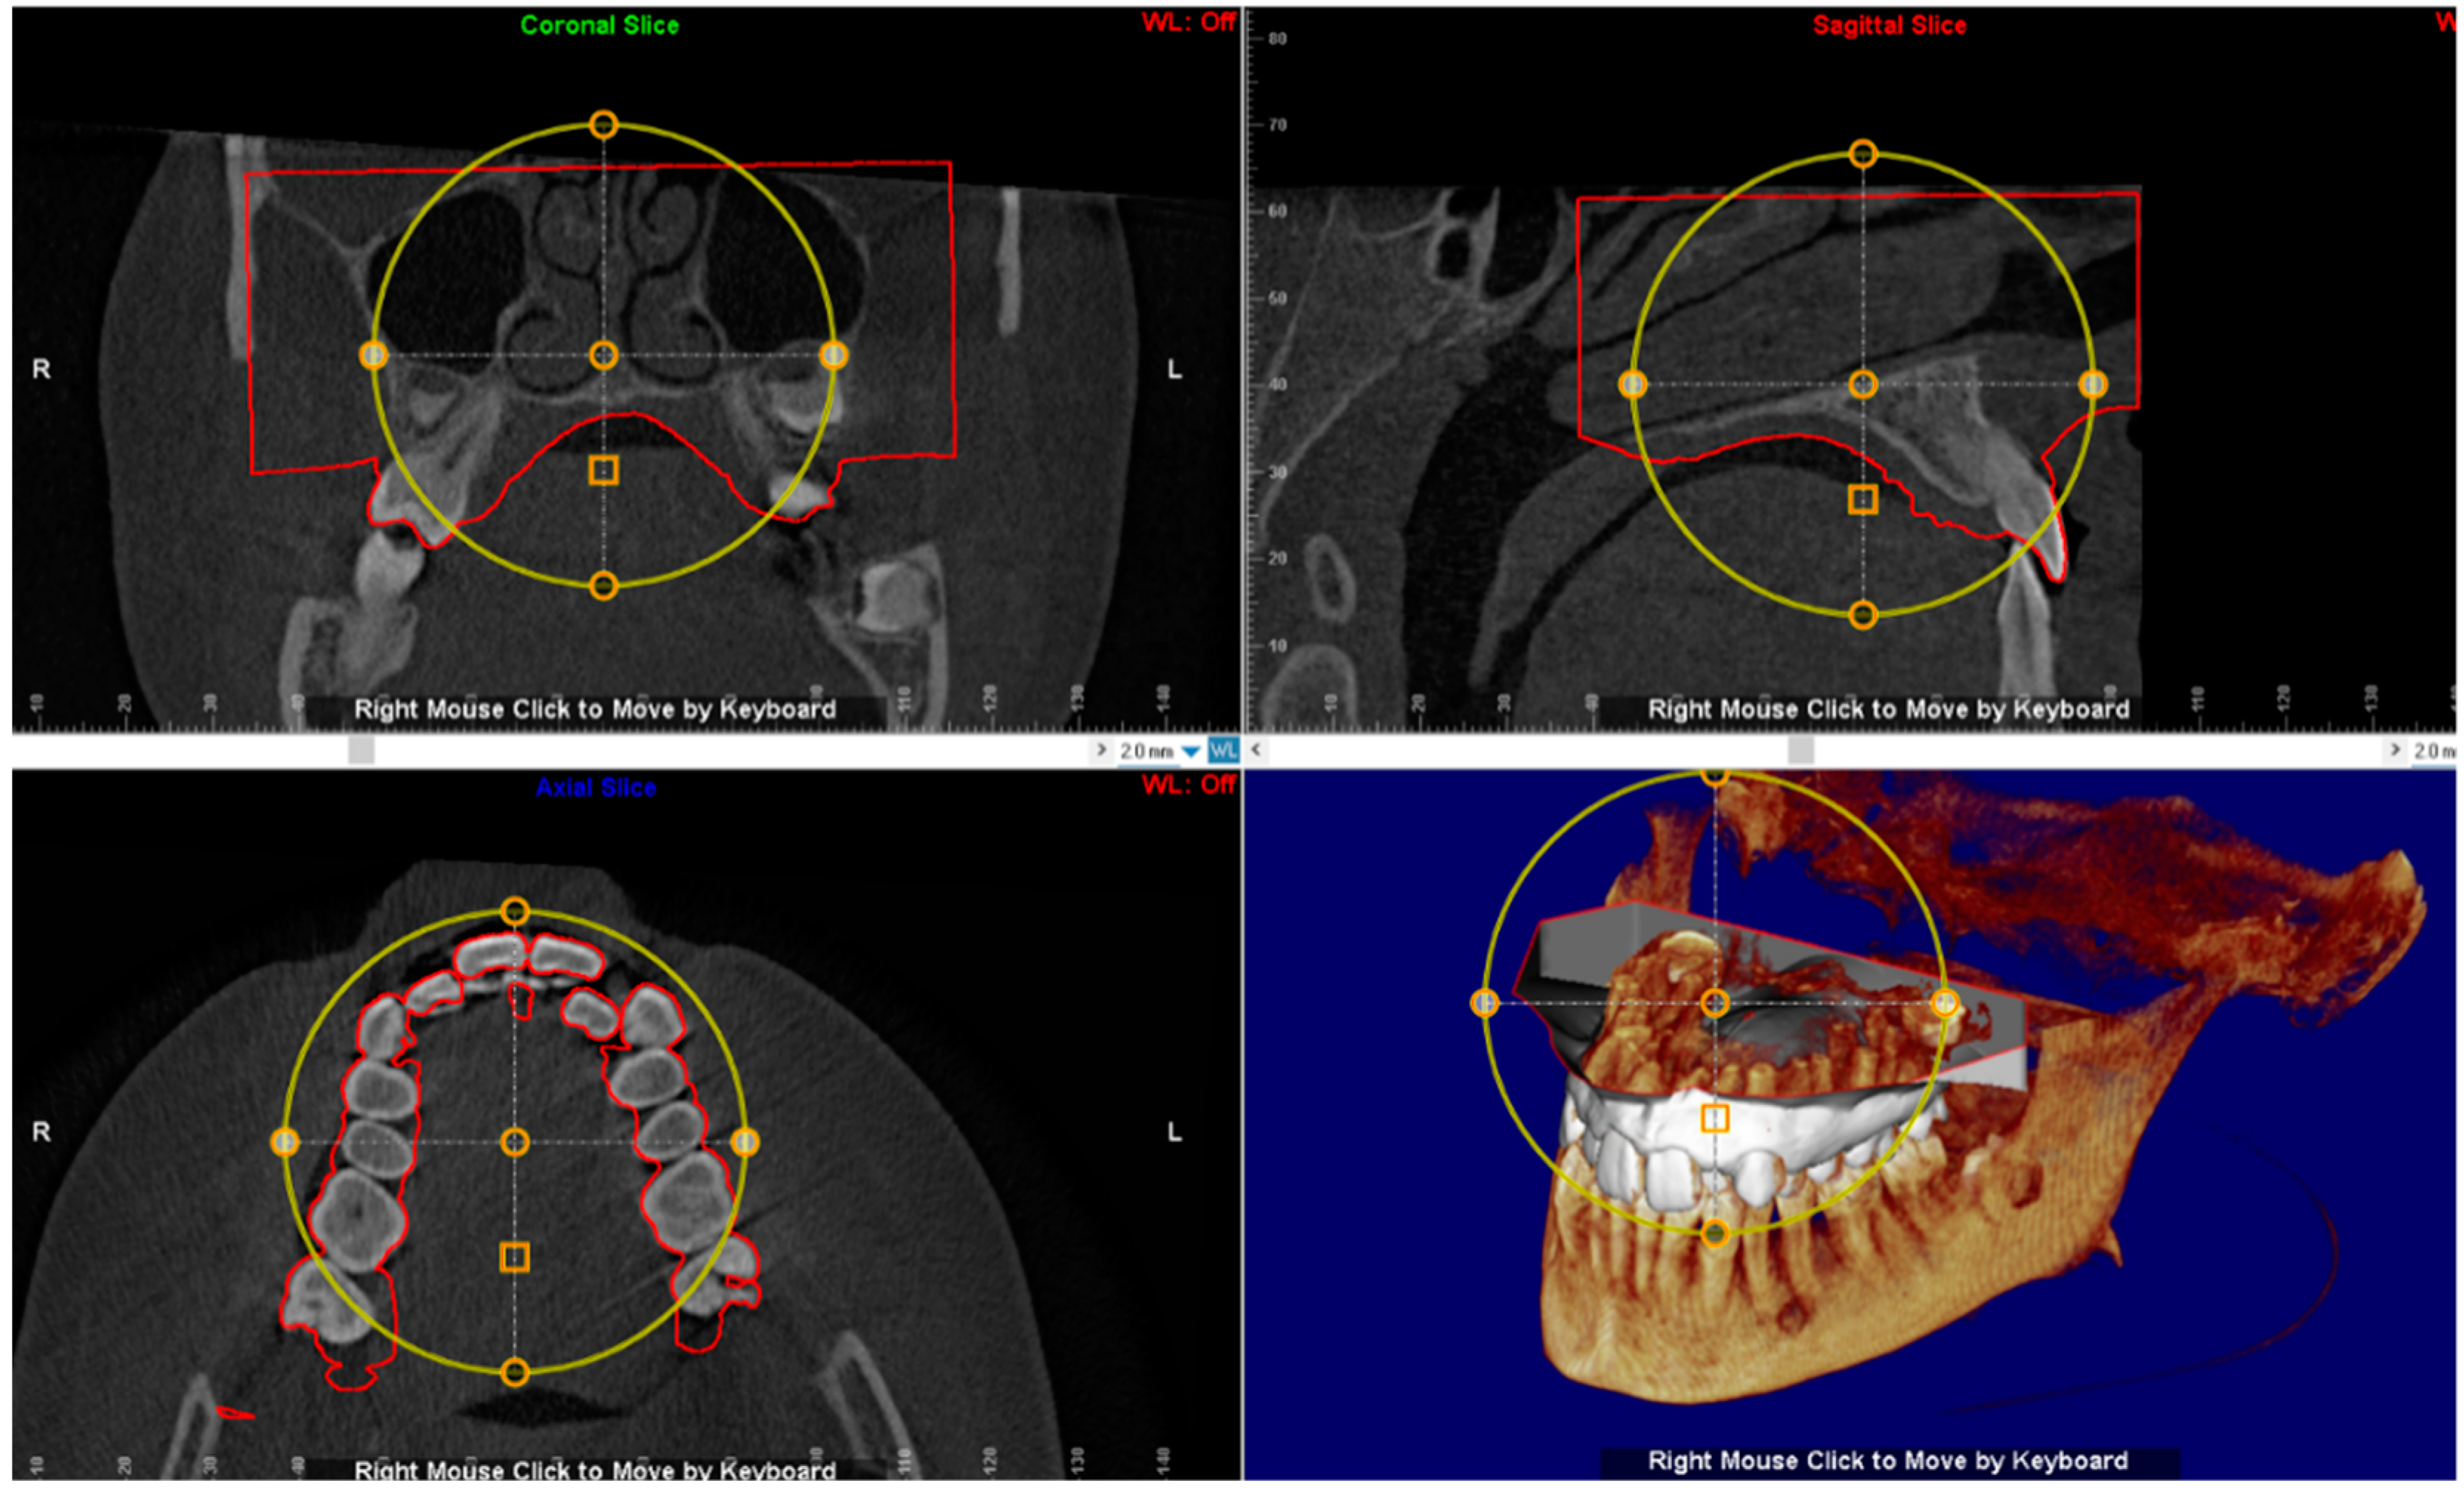

2.3. CBCT Examination

3.2. Digital Workflow for Planning MSE Device